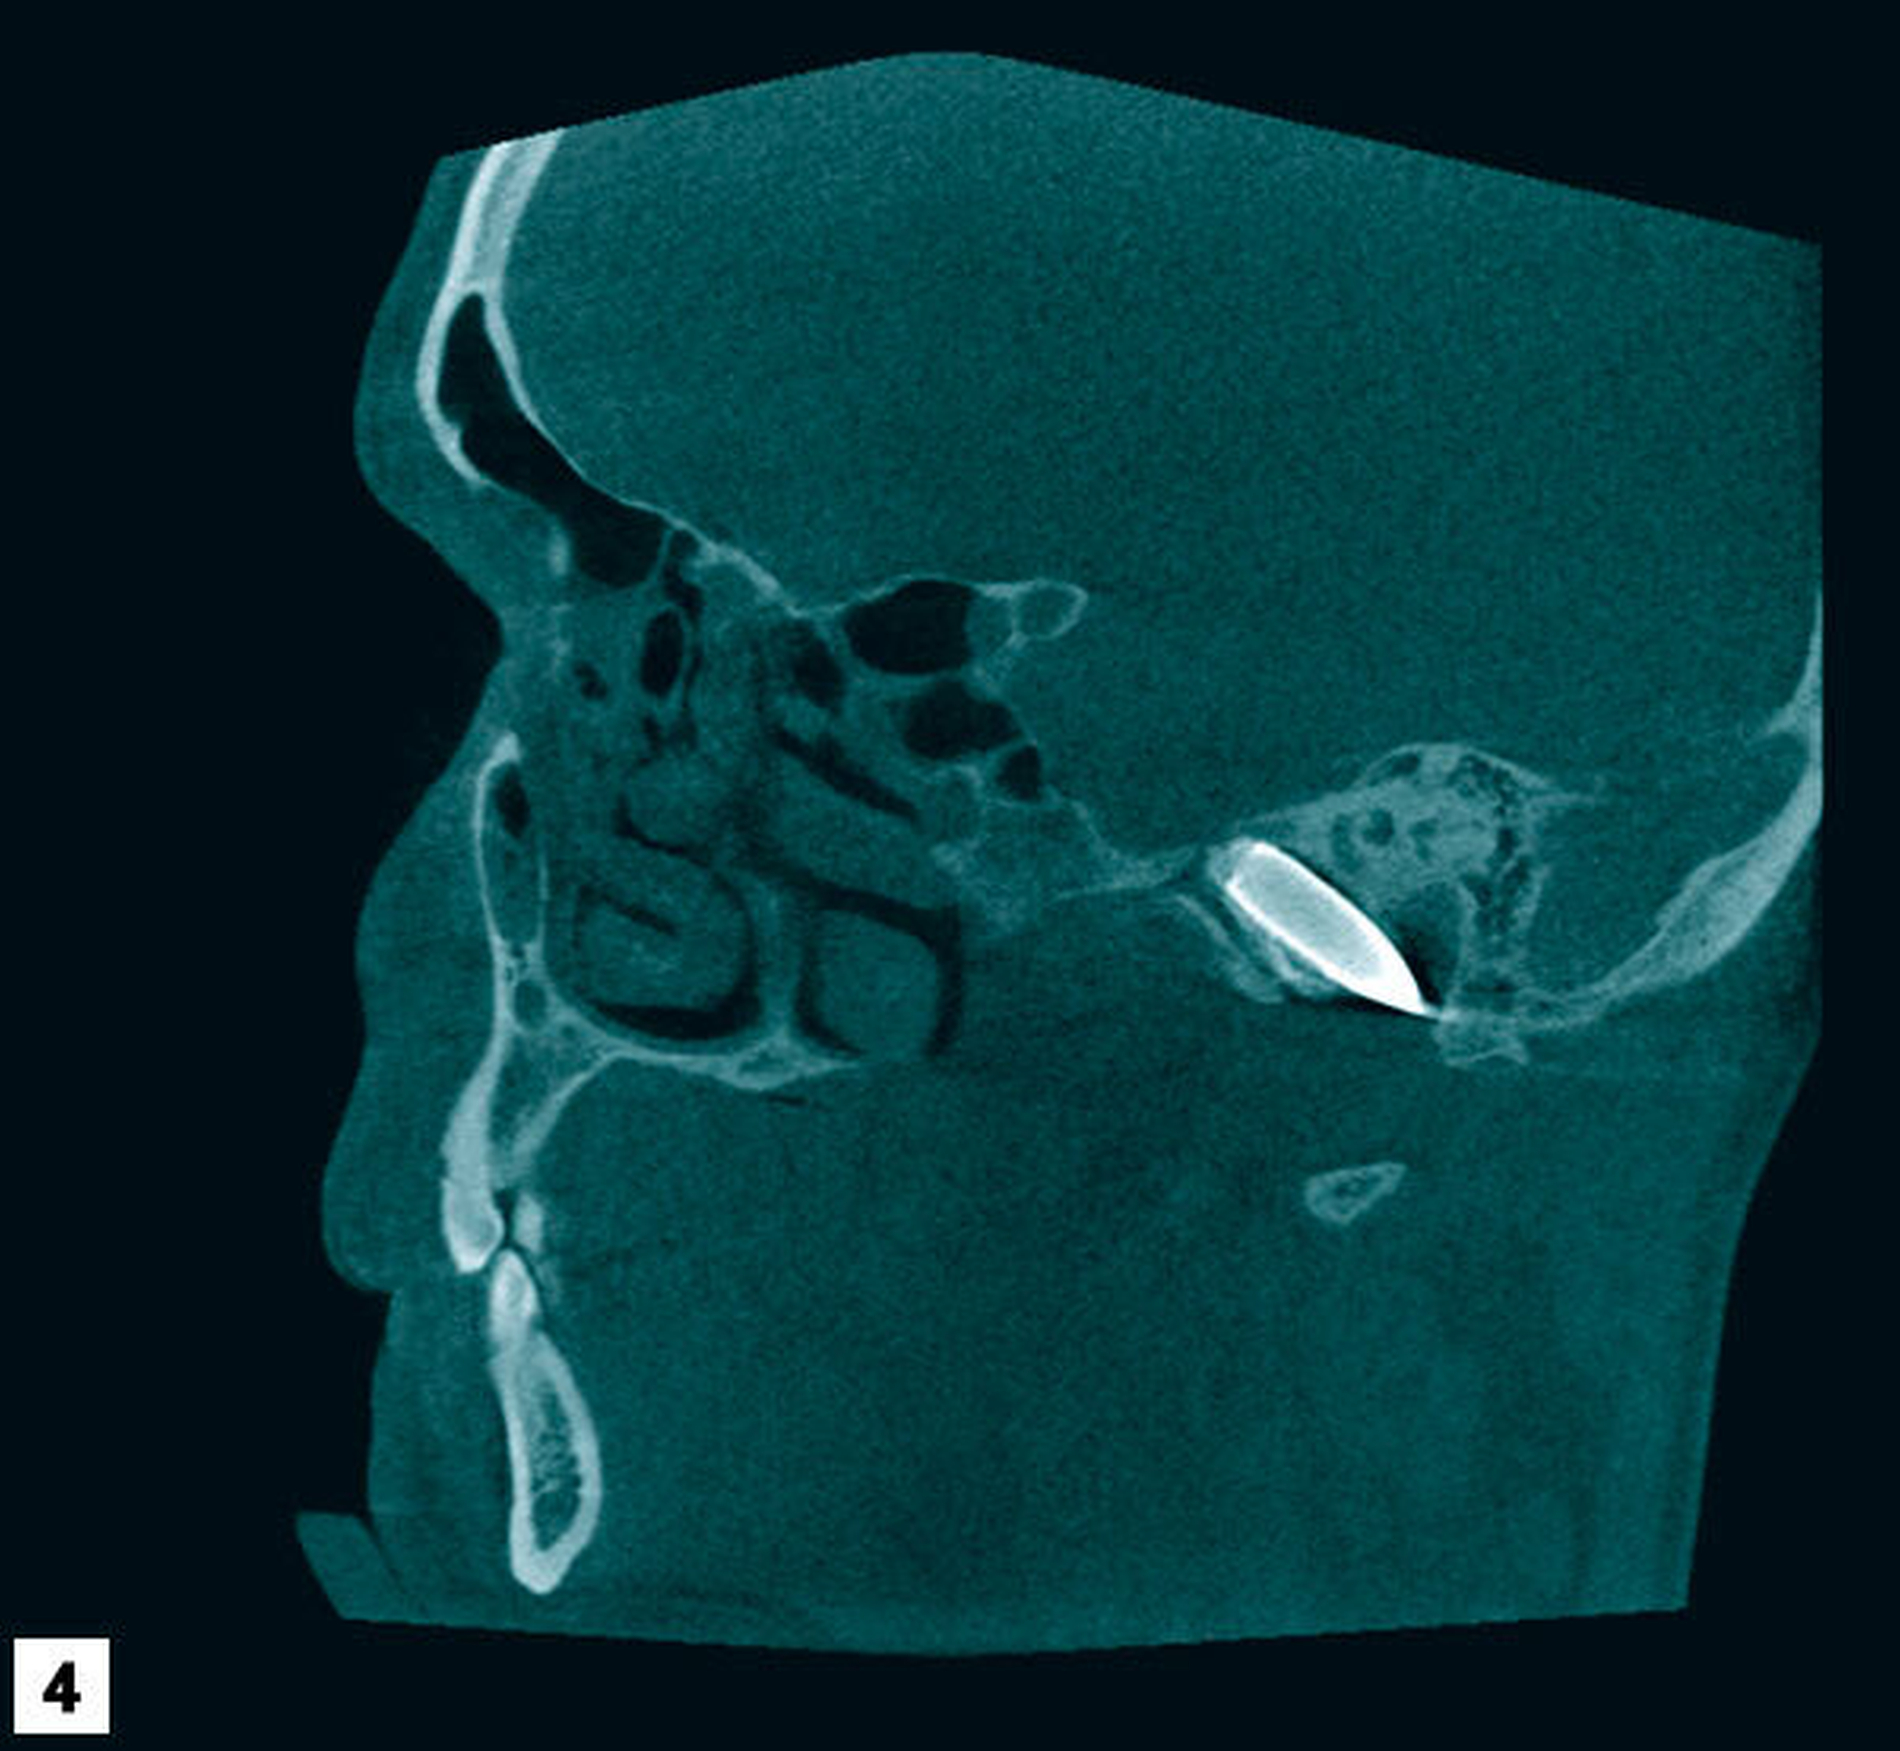

Zur weiteren Lokalisation in der dritten Ebene wurde eine Digitale Volumentomografie veranlasst. Diese Bilder zeigten neben einer großen Osteolyse apikal des Zahns 37 und deutlicher Schleimhautschwellung im Bereich der Sinus maxillares und ethmoidales einen metalldichten Fremdkörper im Bereich der Schädelbasis mit einer Ausdehnung von circa 7 mm x 38 mm mit einer projektiltypischen Form (Abbildungen 4 bis 6). Die Recherche lässt vermuten, dass dieses Projektil als Munition für ein Automat Kalaschnikow 47 Sturmgewehr (AK 47, wahre Größe der Kurzpatrone M 43 = 7,62 mm x 39 mm) passt.